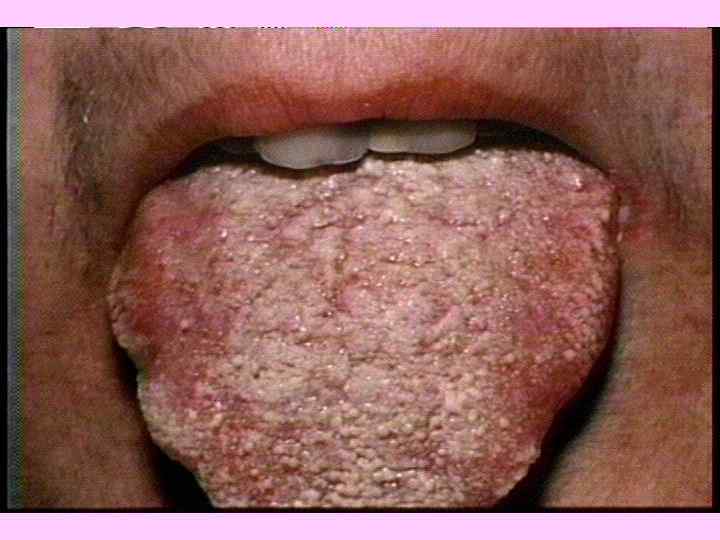

1839 г. УСТАНОВЛЕНА ГРИБКОВАЯ ПРИРОДА ПАРШИ (Trichophyton schoenleini) ОБНАРУЖЕНА Саndida albicans ПРИ МОЛОЧНИЦЕ 1892 г. ОТКРЫТ ВОЗБУДИТЕЛЬ СИСТЕМНЫХ МИКОЗОВ (Coccidioides immitis)